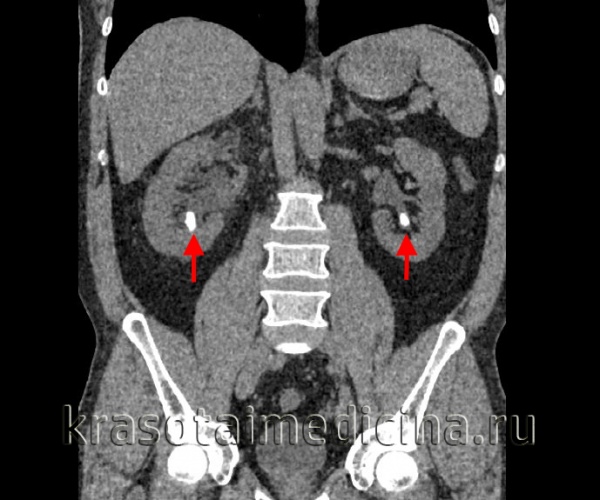

КТ и рентгенография при мочекаменной болезни (МКБ)

КТ ОБП и забрюшинного пространства. Плотные конкременты в нижних чашечках с обеих сторон. (фото Вишняков В.Н.)